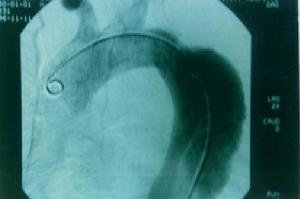

主動脈夾層動脈瘤(二)X線 胸部平片見上縱隔或主動脈弓影增大,主動脈外形不規則,有局部隆起。如見主動脈內膜鈣化影,可準確測量主動脈壁的厚度。正常在2~3mm,增到10mm時則提示夾層分離可能性,若超過10mm則可肯定為本病。主動脈造影可以顯示裂口的部位,明確分支和主動脈瓣受累情況,估測主動脈瓣關閉不全的嚴重程度。缺點是它屬於有創性檢查,術中有一定危險性。CT可顯示病變的主動脈擴張。發現主動脈內膜鈣化優於X線平片,如果鈣化內膜向中央移位則提示主動脈夾層,如向外圍移位提示單純主動脈瘤。此外CT還可顯示由於主動脈內膜撕裂所致內膜瓣,此瓣將主動脈夾層分為真腔和假腔。CT對降主動脈夾層分離準確性高,主動脈升、弓段由於動脈扭曲,可產生假陽性或假陰性。但CT對確定裂口部位及主動脈分支血管的情況有困難,且不能估測主動脈瓣關閉不全的存在。

(五)數字減影血管造影(DSA) 無創傷性DSA對B型主動脈夾層分離的診斷較準確,可發現夾層的位置及範圍,有時還可見撕裂的內膜片,但對A型病變診斷價值較小。DSA還能顯示主動脈的血流動力學和主要分支的灌注情況。易於發現血管造影不能檢測到的鈣化。

目前StanfordB型(相當於DeBakeyIII型)的首選經皮覆膜支架置入術,必要時外科手術治療。